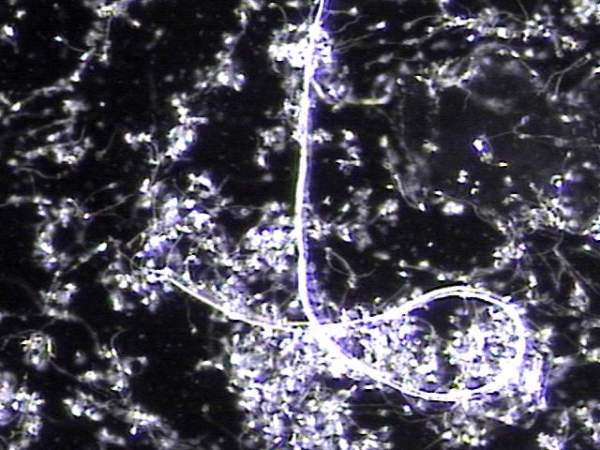

주 2회 전립선과 정낭 그리고 정관등의 표적 치료중 정관을 막고 있는 거짓중층원주상피세포와 사정되지 못한 정자들과 단백질등의 치료된 현미경학적 자료입니다.

This microscopic image was taken after repeated targeted treatment.

It shows that old cells, proteins, and sperm had collected and blocked the vas deferens.

The size of this material confirms that it was stuck inside the vas deferens.

The treatment helped to remove this blockage, allowing the ducts to open and improving the flow of semen.

사진 속 현미경 영상은 정관에서 배출된 치료 후 내용물로 보입니다. 관찰되는 소견을 근거로 말씀드리면:

길게 뻗은 섬유성 구조와 세포성 잔여물이 함께 보입니다.

이는 흔히 노화된 거짓중층원주상피세포, 단백질 덩어리, 또는 정자와 점액질이 엉겨 붙은 물질일 가능성이 높습니다.

직경이 비교적 크고 길게 뭉친 형태를 띠기 때문에, 정관 내강을 막아 정액의 흐름을 방해했을 것으로 추정됩니다.

즉, 정관을 막고 있던 주된 원인은

오래된 상피세포 찌꺼기, 단백질 응집물, 그리고 사정되지 못하고 고여 있던 정자들이 엉겨 형성된 덩어리(blockage material) 로 보입니다.

This microscopic image shows material that was removed after targeted treatment of the vas deferens.

The findings suggest that the blockage was mainly caused by:

- Old cells that had shed from the lining,

- Protein debris, and

- Sperm that could not be released and became trapped.

These substances clumped together over time and formed a plug large enough to block the vas deferens, preventing normal flow.

The treatment helped clear this material, allowing for better passage through the duct.